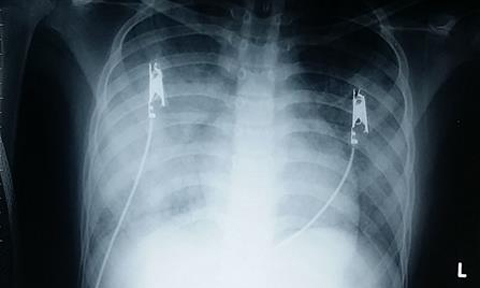

Các xét nghiệm ban đầu cho thấy tình trạng viêm phổi của bé nặng với XQ ngực thâm nhiễm lan tỏa 2 phế trường. Nguồn ảnh: Công an Nhân dân.

Khi được đưa đến BV Nhi Đồng 2, các xét nghiệm ban đầu cho thấy tình trạng viêm phổi nặng, chụp x-quang ngực thâm nhiễm lan tỏa 2 phế trường nhưng các xét nghiệm nhiễm trùng không tăng nhiều.